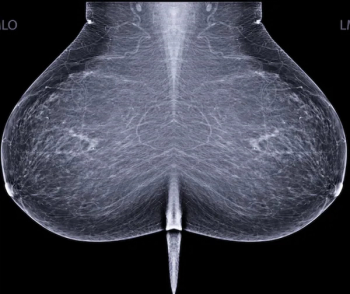

An emerging deep learning algorithm had a lower AUC and sensitivity than urological radiologists for differentiating between small renal masses on computed tomography (CT) scans but had a 21 percent higher sensitivity rate than non-urological radiologists, according to new research.